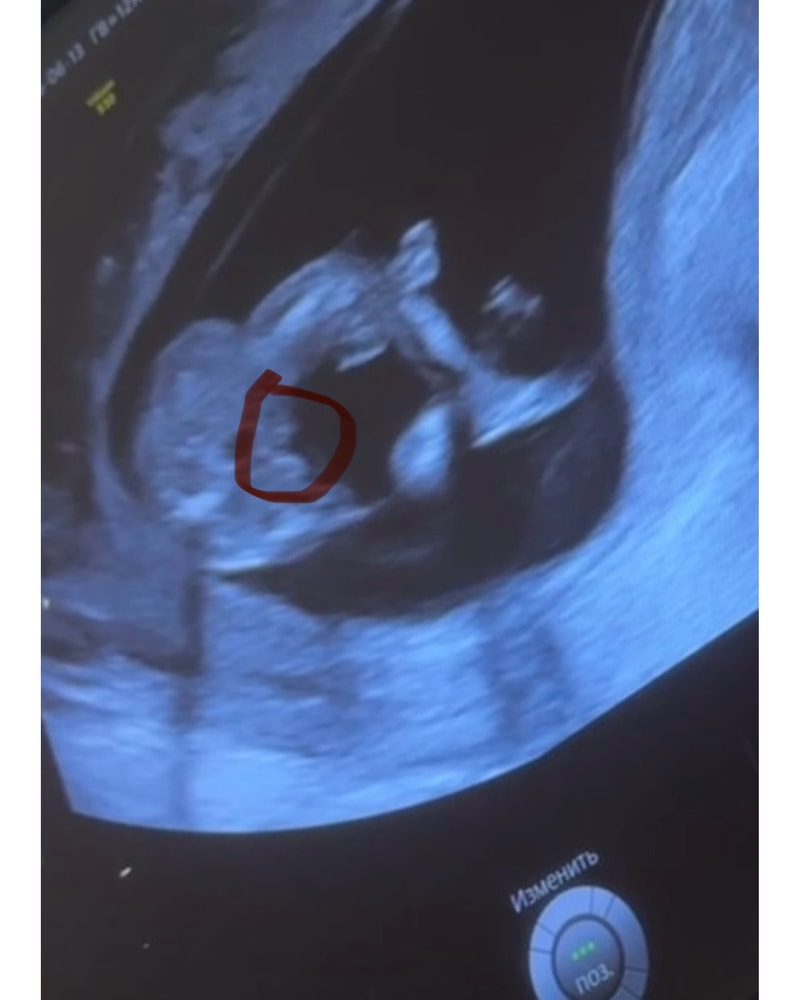

2 фото - закинул ножку на ножку, вид со стороны попы (снизу)

Что видите на 2 фото, мальчик, девочка? Я пока ничего, через 8 дней на НИПТ узнаю точно 100%

Кактусеныш, блин, я часами уже смотрю и думаю, это ведь не похоже не пенис? Потому что как будто похоже 😆😭

Mia, да нет) Скорее «пирожок» вижу

Но могу ошибиться. Но это точно не пенис))